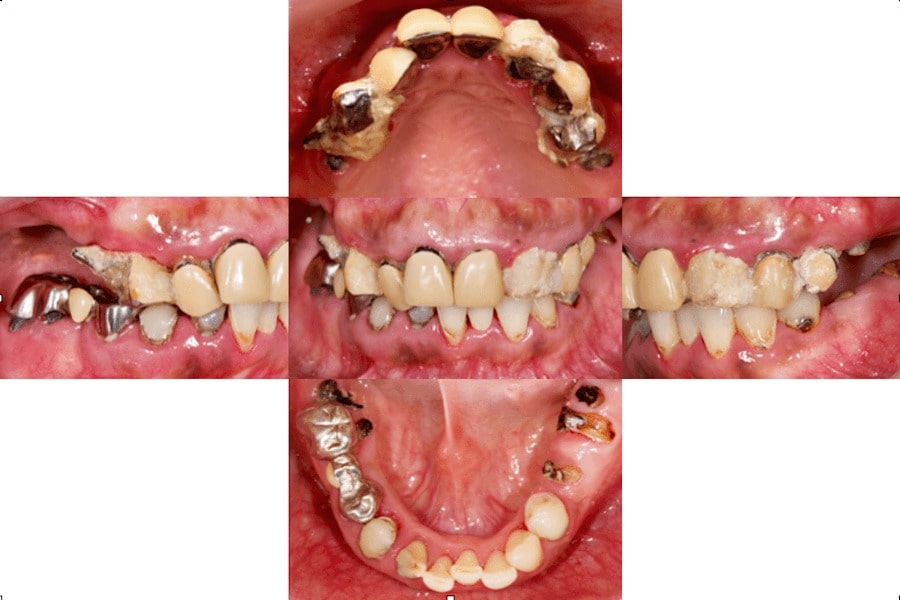

パノラマX線

上顎:

残っている歯の根っこの部分が、ほとんど破折しており保存不可能

下顎:

前歯部は生活歯(神経がある)であり保存可能、臼歯部は保存不可能